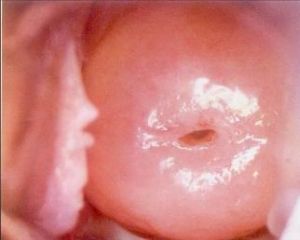

(2)在宮頸腺體的深部可能出現粘液瀦留,形成大小不等的囊腫導致。有時可比正常宮頸增大2~4倍,宮頸表面可以是光滑的,也可有糜爛。宮頸質地一般較硬,這是纖維結締組織增生所致的。

區別

宮頸肥大和腺體囊腫也是慢性宮頸炎常見的一種表現,宮頸肥大和腺體囊腫可以單獨存在,也可以同時發生。前者是指宮頸體積的增大,後者是由於種種原因造成腺體開口的閉鎖,腺體分泌物瀦留而形成囊腫。 引起宮頸肥大的原因是:由於慢性炎症的長期刺激,宮頸組織發生充血、水腫,宮頸腺體及間質增生,腺管受周圍增生組織的擠壓,使腺體產生的粘液難以排出,而形成瀦留囊腫,較表淺的腺體囊腫向宮頸表面突出,很容易觀察到,而深部的腺體囊腫常導致宮頸呈不同程度的增粗、變大,一般習慣稱之為宮頸肥大。深部腺體囊腫肉眼觀察難以發現,但做B超檢查時可見到宮頸肌壁間有大小不等的圓形液性暗區。 肥大的宮頸表面由於損傷或炎症刺激也可以出現鱗狀上皮脫落、柱狀上皮增生而形成糜爛。當炎症經過治療後,宮頸局部充血水腫消退,宮頸表面重新被鱗狀上皮覆蓋,又恢復為光滑狀。但是,增生的結締組織並不消退,依然存在,故宮頸仍維持其肥大的外觀,有時甚至可增大1~2倍以上。 宮頸肥大和腺體囊腫的主要臨床症狀為白帶增多。另外,由於結締組織增生及炎症沿宮頸旁或經宮骶韌帶向盆腔擴散,故患者經常主訴有腰骶部疼痛或會陰部墜脹感,這是宮頸肥大比較突出的2個症狀。 宮頸肥大的陰道鏡所見:宮頸明顯增大,由於局部慢性炎症刺激引起宮頸瘀血,宮頸表面呈青灰色,鱗狀上皮較厚,在鱗柱交界區可見數量不等的青白色或淡黃色瀦留囊腫,囊腫表面可見分支血管,囊內容物為膠凍樣粘液。宮頸表面可呈光滑狀或糜爛狀,糜爛面塗3%醋酸後呈“葡萄串”改變。鱗狀上皮區有時可見到粗大血管,分支較差。 子宮頸糜爛必須與早期宮頸癌相鑑別,後者一般質地較硬、脆,極易出血,而子宮頸糜爛較軟、潤滑,雖有出血傾向,僅在檢查觸及後在指套上染有血跡。但大多數早期子宮頸癌在臨床上不藉助其他診斷方法,不可能與子宮頸糜爛相鑑別。因而凡有子宮頸糜爛者,均應常規作宮頸刮片檢查找癌細胞,必要時在陰道鏡檢查下作活檢。